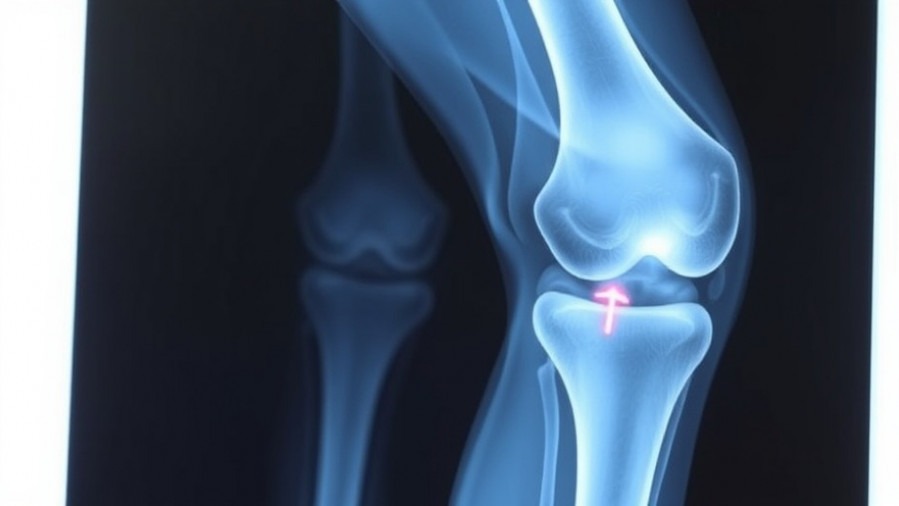

Are You Resurfacing Patella During TKA? What New Guidelines Suggest

As healthcare professionals, especially those running concierge medical practices, it's crucial to stay informed about evolving surgical techniques and their implications for patient care. Recent findings from the American Association of Hip and Knee Surgeons Annual Meeting suggest that patella resurfacing during total knee arthroplasty (TKA) may not produce the improved outcomes previously assumed for patients with inflammatory arthritis. Dr. Ilya Bendich and his colleagues emphasized that the data collected showcases no significant differences in outcomes—such as reoperations, complications, or anterior knee pain—when comparing patients who underwent resurfacing versus those who did not.

In a carefully constructed study, the researchers analyzed data from patients who underwent TKA, observing 38 patients who received patella resurfacing against 348 who did not, matched for age, BMI, and sex. The results showed that the surgical decision to resurface the patella could be reconsidered. Despite nearly 90% of total knee replacements currently involving patella resurfacing in the United States, these findings suggest a potential paradigm shift, encouraging physicians to evaluate the necessity of resurfacing on a case-by-case basis. This aligns with emerging trends advocating for personalized patient care strategies in concierge medicine.